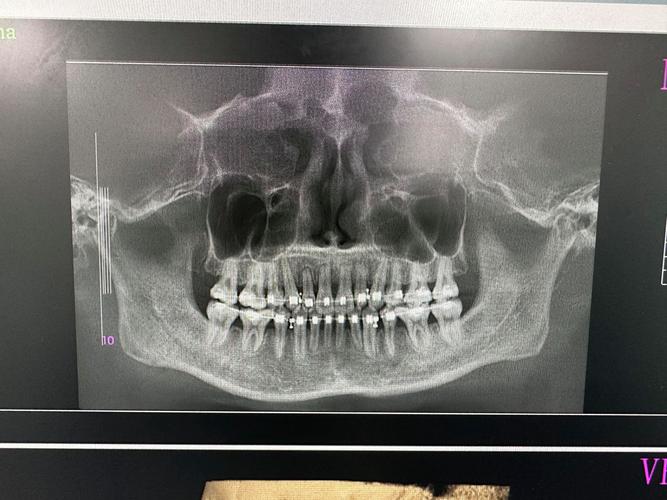

- 矫正前全面评估:拍摄根尖片、曲面断层片,必要时进行CBCT检查,评估牙根形态、长度及根尖周状况;对高风险患者(如遗传易感、牙根形态异常)制定个性化方案。

- 影像学检查:根尖片是基础检查方法,可观察牙根长度变化;CBCT可三维评估吸收部位、深度及范围,对早期吸收(<0.3mm)更敏感。